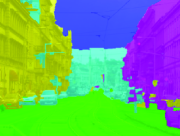

Appearance is one of the most important visual cues to distinguish between different structures in an image. Appearance is described by studying the distribution of different features such as intensity values in gray-scale images, color, and texture inside each object. In most cases, appearance models are incorporated into the data term in (2) and (7). The purpose of incorporating appearance prior is to fit the appearance distribution of the segmented objects to the distribution of objects of interest, e.g. using Gaussian mixture model (GMM) (Rother et al., 2004). In the literature, there are two ways to model the appearance: 1) adaptively learning the appearance during the segmentation procedure, and 2) knowing the appearance model prior to performing segmentation (e.g. by observing the appearance distribution of the training data). In the former case, the appearance model is learned as the segmentation is performed (Vese and Chan, 2002) (computed online). In the second case, it is assumed that the probability of each pixel belonging to particular label is known, i.e. if represents a particular set of feature values (e.g. intensity/color) associated with each image location for object, then it is assumed that is known (or pre-computed offline). This probability is usually learned and estimated from the distribution of features inside small samples of each object. Figure 9 illustrates the probability of different structures (the kidney, the tumour, and the background) in an endoscopic scene. A lower intensity in Figures 9(b-d) corresponds to higher probability.